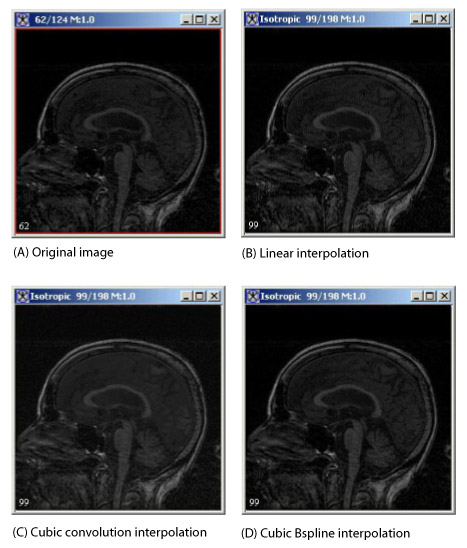

This section shows the equations that MIPAV uses for the three interpolation methods for the algorithm. Figure 1 shows an original image and the resulting images after linear, cubic convolution, and cubic B-spline interpolation are applied, see also "Interpolation methods used in MIPAV".

Figure 1. Reslice-Isotropic Voxels algorithm applied to an image